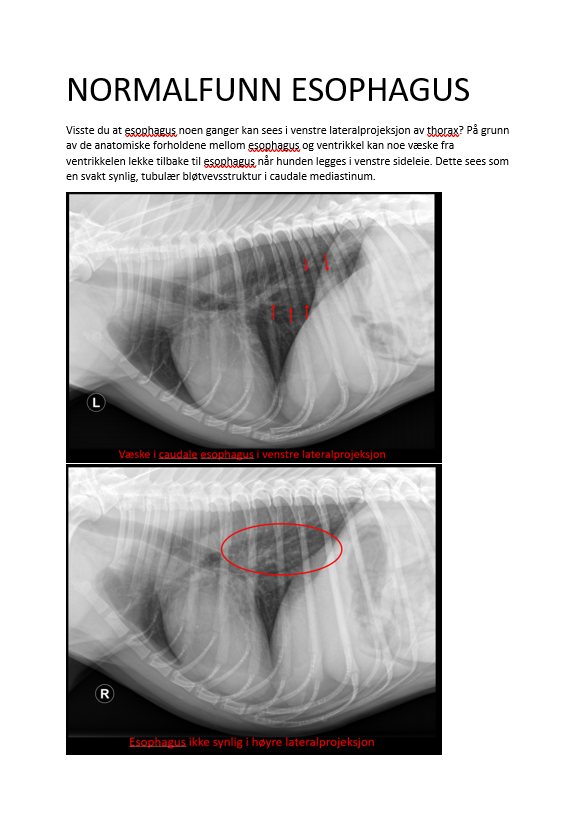

NORMALFUNN ESOPHAGUS